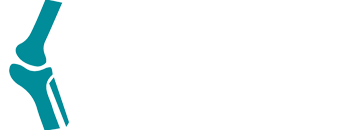

Axial deviations in the knee refer to situations where the axis of the knee deviates from its normal state, which should be straight and in line. These deviations can be internal (varus) or external (valgus).

Varus occurs when the knee bends inward. This condition may occur due to various factors, including muscle weakness, knee injuries or diseases, traumas, excessive body weight or muscle tension.

In contrast, valgus occurs when the knee deviates outward. The causes of this deviation are similar to internal axis deviation and may occur due to muscle weakness, knee injuries or diseases, traumas, excessive body weight or muscle tension.